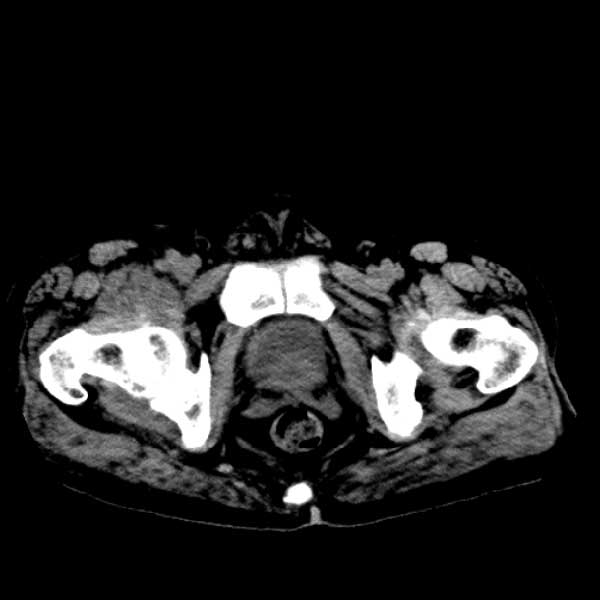

标题: CT13513:男 71 腹部疼痛20余天,近几天高热就诊,骨窗未见异 [打印本页]

标题: CT13513:男 71 腹部疼痛20余天,近几天高热就诊,骨窗未见异

考虑感染性病变可能性大,起源于阑尾?

感染,脓肿形成

考虑为化脓性阑尾炎.脓肿形成.及多肌肉累及.

考虑右侧腰大肌脓肿,向右髂窝、右腹股沟流注。

支持化脓性阑尾炎伴右髂窝脓肿、腰大肌腰方肌脓肿形成。

考虑腹腔及盆腔化脓性炎症,累及右侧髋关节及腹股沟区.

首先考虑化脓性阑尾炎伴腰大肌、腰方肌脓肿,不除外回盲部结核。

回盲部癌待排除。

患者肠镜检查考虑结肠癌,病理证实

患者肠镜检查考虑结肠癌,病理证实。肺部ct可见多发结节,考虑转移